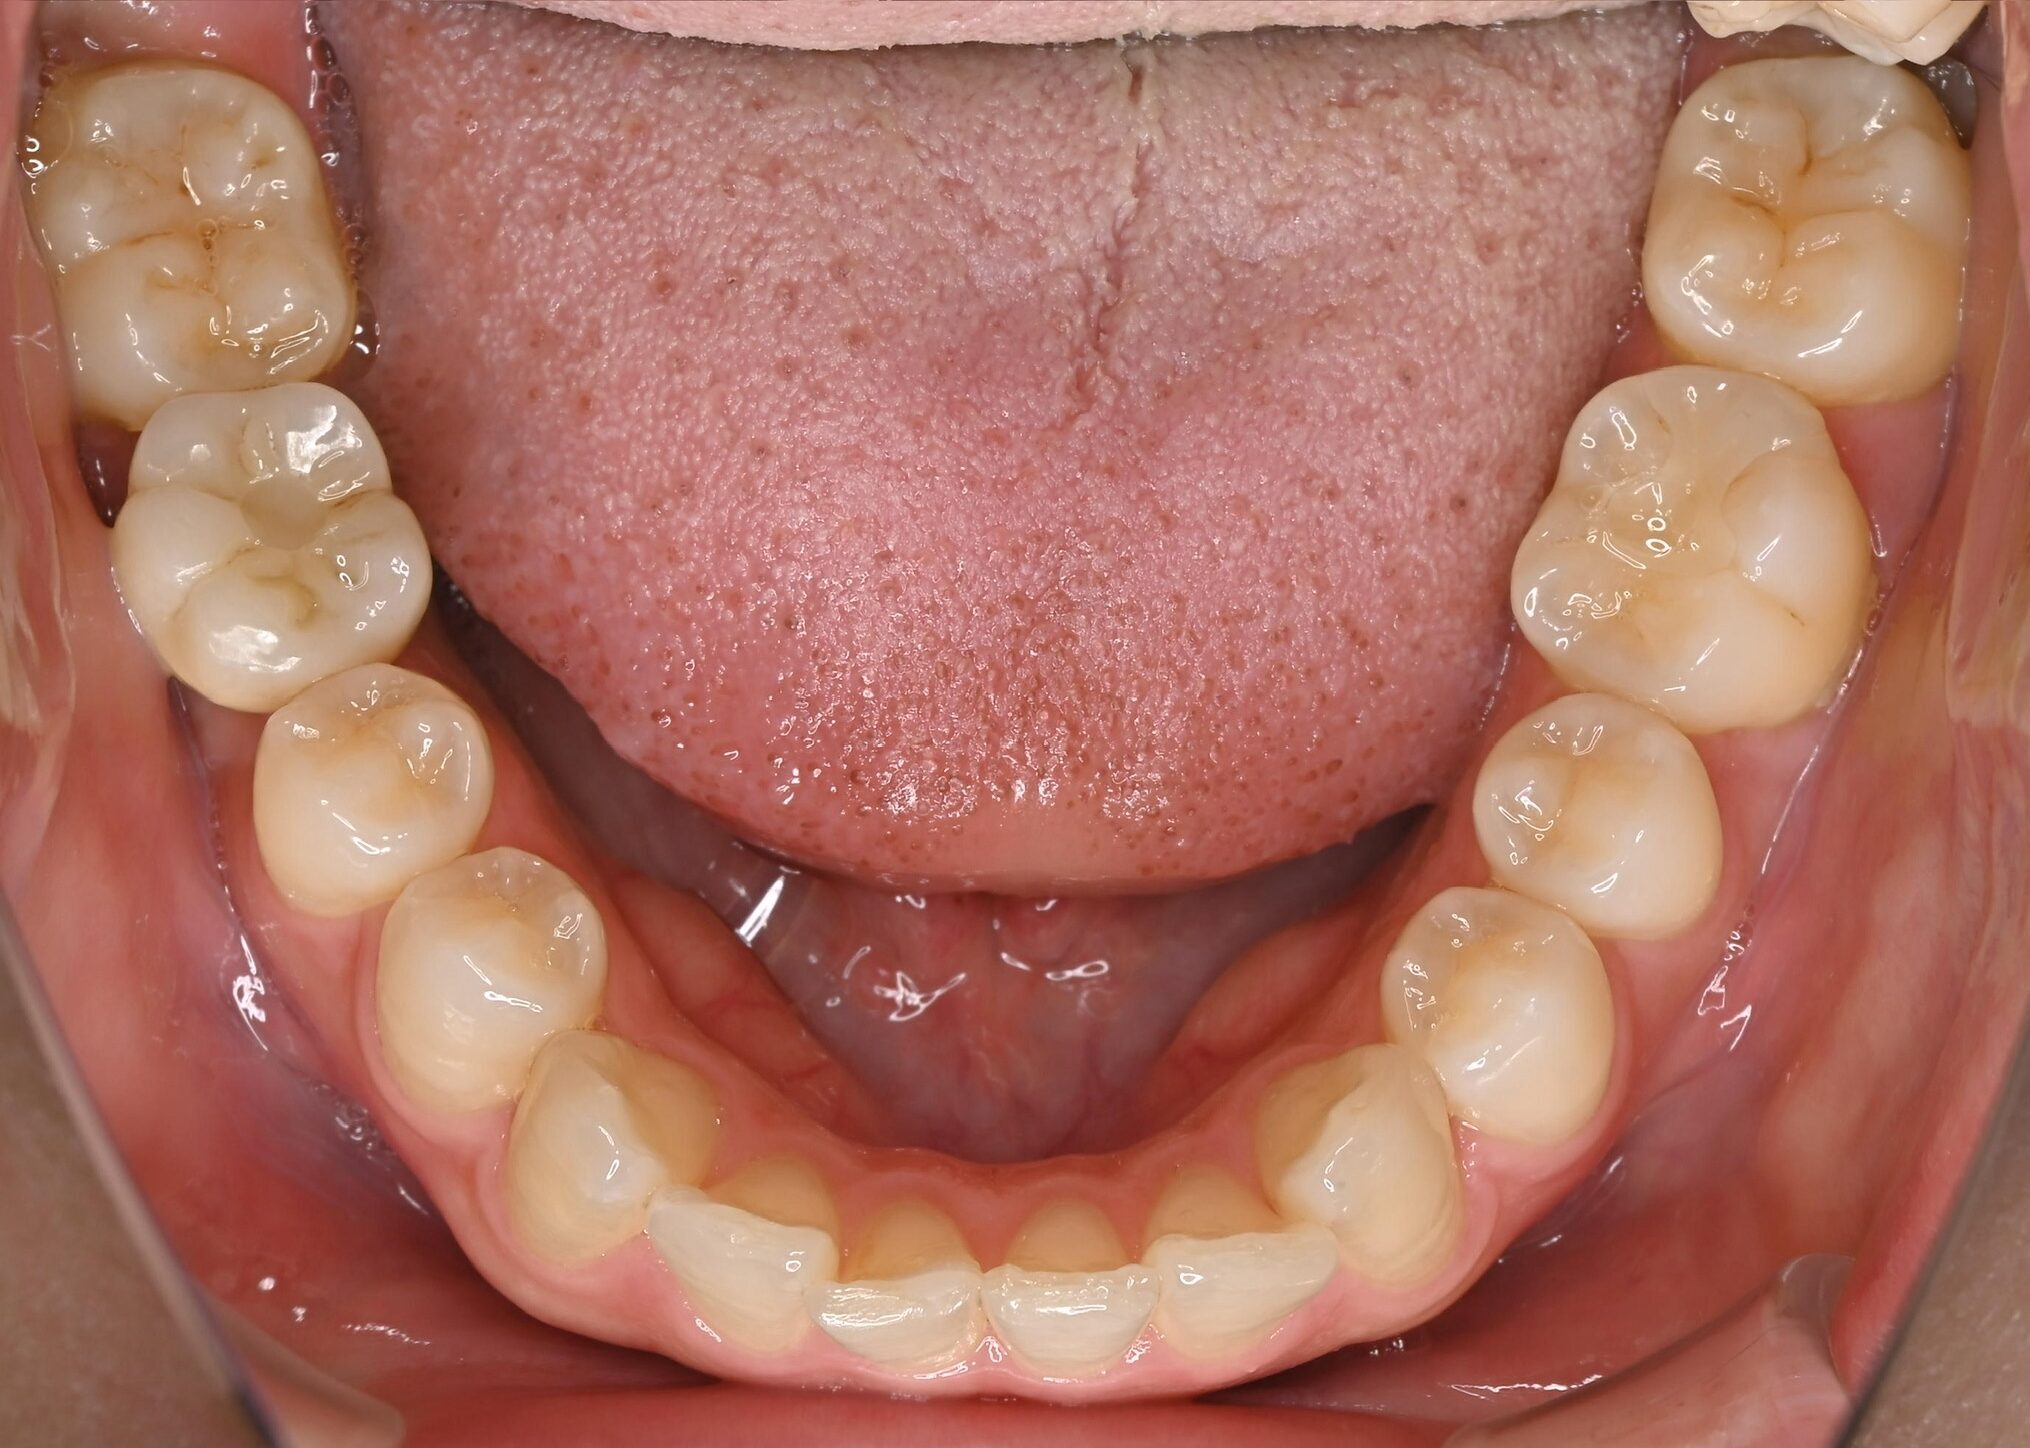

右下奥歯のインプラント症例

Before

• 右下6番欠損です。

• インプラントを埋入するのと同時にヒーリングキャップを取り付けました。

After

治療内容

右下の奥歯を根の先の膿が原因で抜歯された患者様です。

ブリッジ治療では両隣の歯を大きく削らないといけない為、インプラント治療を希望されました。

骨の治り方が歪で、頬側の骨が大きく足りないため骨造成を行い、インプラントを埋入した日にヒーリングキャップを装着し、インプラントが骨と結合するまで待ちます。

その後、型取りをし被せ物をスクリューにて装着しています。

担当歯科医師:平沼 佳朗

治療期間・回数

約10か月

費用

骨造成込み ¥616,000

リスク・副作用

術後に痛みや腫れ、出血を伴います。

口腔内の清掃不良によりインプラントの歯周病(インプラント周囲炎)になる可能性があります。定期的なメインテナンスが必要です。